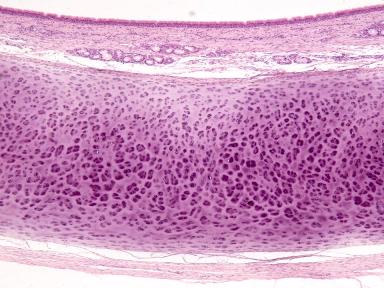

Cartílago hialino